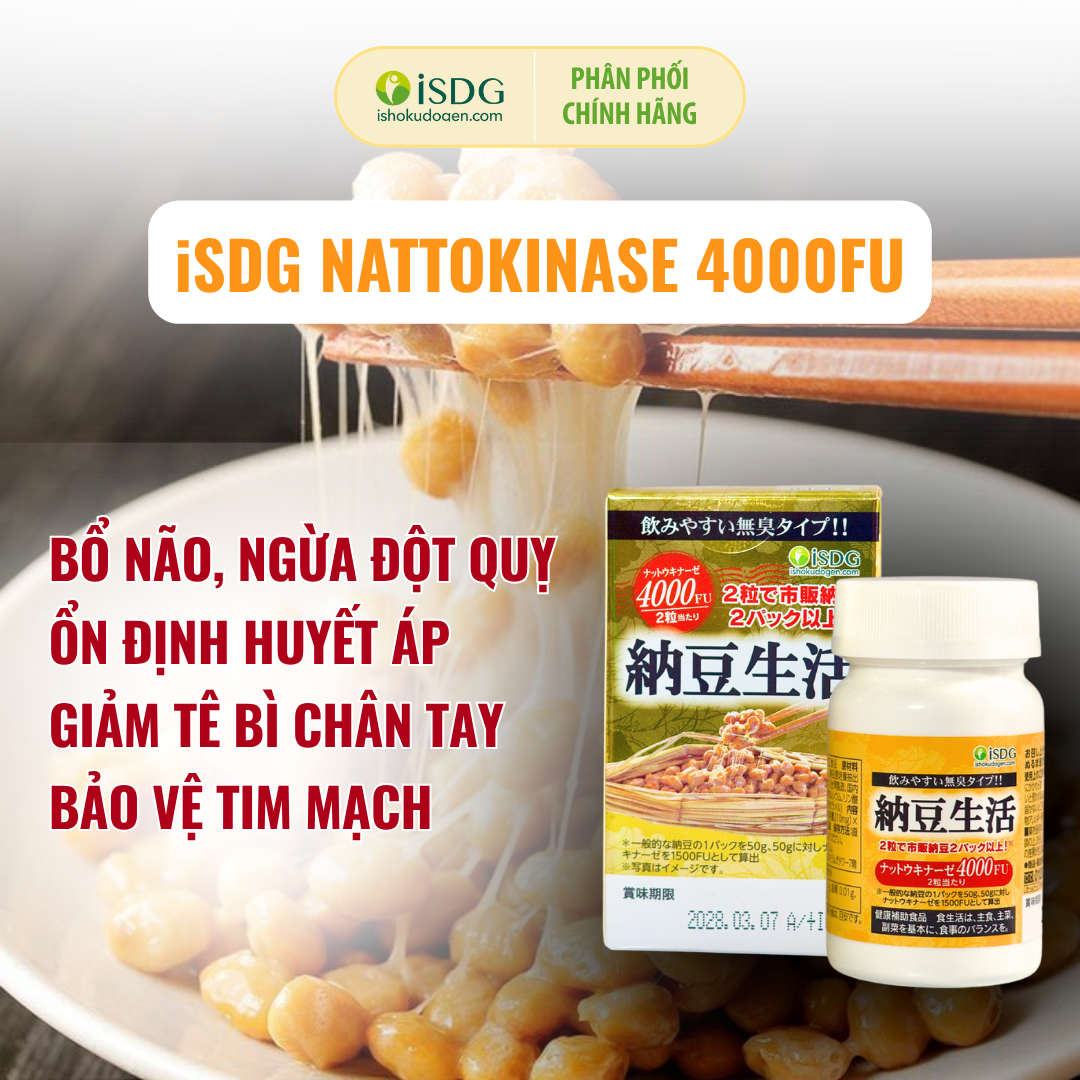

Viên uống iSDG Nattokinase 4000FU

Sản phẩm này được bổ sung hàm lượng Nattokinase gấp đôi so với liều dùng thông thường (2000FU), giúp hỗ trợ giảm thiểu những vấn đề liên quan đến tim mạch và mạch máu hiệu quả. Nattokinase là một loại enzyme được tìm thấy trong món ăn Natto của Nhật Bản, có tác dụng làm tan cục máu đông, ngăn ngừa xơ vữa động mạch, giảm nguy cơ tai biến mạch máu não, nhồi máu cơ tim, đột quy.

Công dụng sản phẩm

Ngăn ngừa các biến chứng đột quỵ

Hỗ trợ làm tan cục máu đông, cải thiện tuần hoàn máu và giảm nguy cơ tắc nghẽn mạch.

Bảo vệ hệ thần kinh

Cải thiện trí nhớ, tăng cường lưu thông máu lên não, hỗ trợ điều trị Alzheimer.

Ngăn ngừa tai biến mạch máu não

Hỗ trợ làm tan cục máu đông, giảm nguy cơ tai biến do tắc nghẽn mạch máu não.

Tăng cường sức khỏe tim mạch

Giúp hạ huyết áp, giảm cholesterol máu, chống xơ vữa động mạch, ngăn ngừa bệnh tim mạch.

Giảm các triệu chứng máu đông

Hỗ trợ lưu thông huyết mạch, giảm tình trạng tê bì, nặng chân tay.

Ngừa huyết khối tĩnh mạch sâu

Giảm nguy cơ huyết khối tĩnh mạch sâu và giãn tĩnh mạch ở chân.